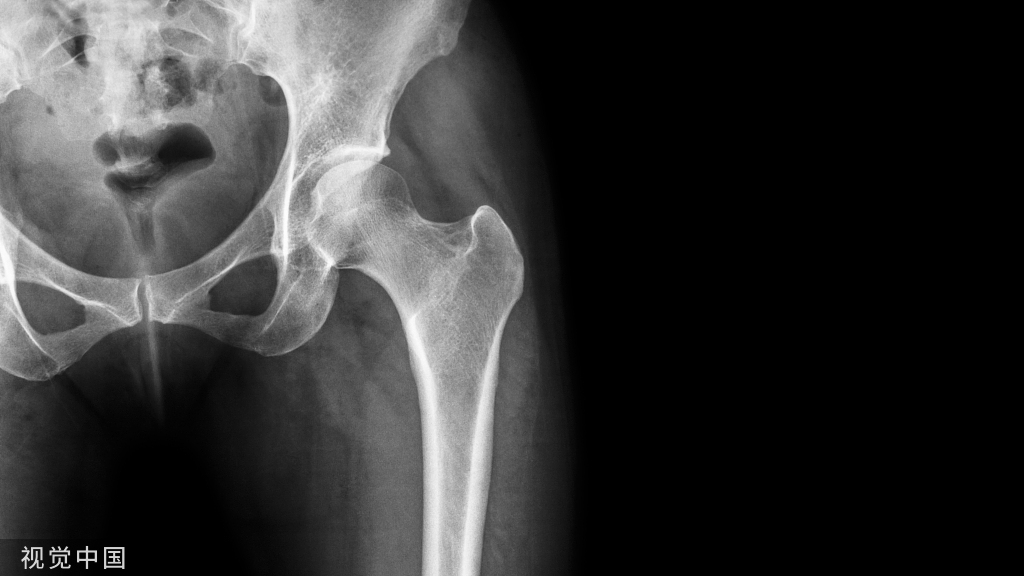

术前X片

术前X线